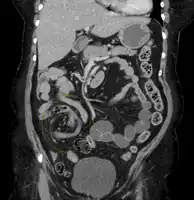

| Coronal CT of the abdomen, demonstrating a volvulus as indicated by twisting of the bowel stock | |